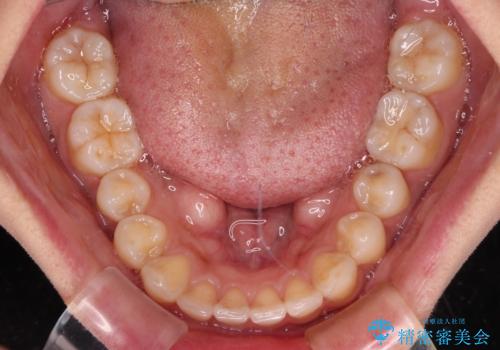

【モニター】歯列が狭くデコボコが気になる 急速拡大装置を用いたインビザライン矯正

上顎骨の幅が下顎骨よりも小さいので、拡大装置により骨幅を広げて上下関係を改善し、その後インビザラインにて歯並びを整えることとしました。

上下の骨幅を改善したことで、スムーズに歯列矯正を行うことができました。

土台のまま放置されていた歯は土台の状態で咬み合っていましたが、急速拡大を行った際に咬み合わせが著しく挙上されたため、その際に土台を大きくすることで咬み合う歯との距離を確保しました。